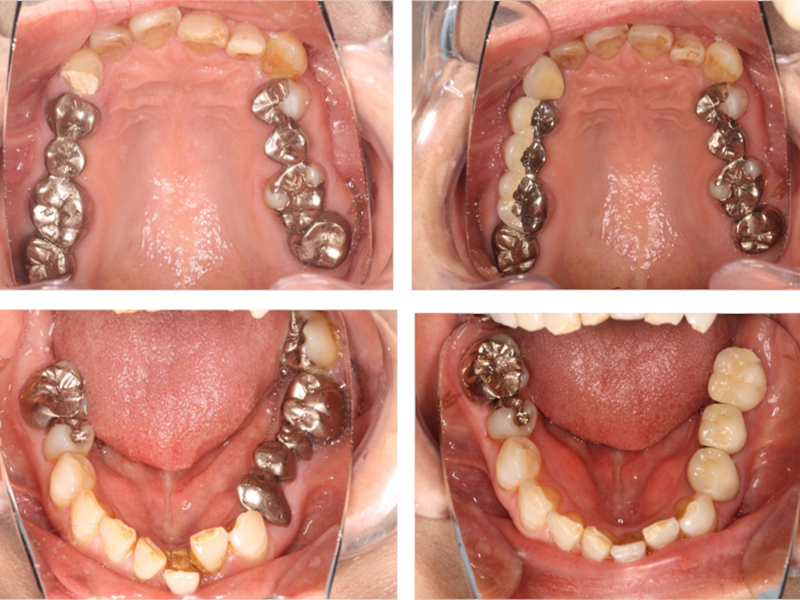

治療終了時

before

after